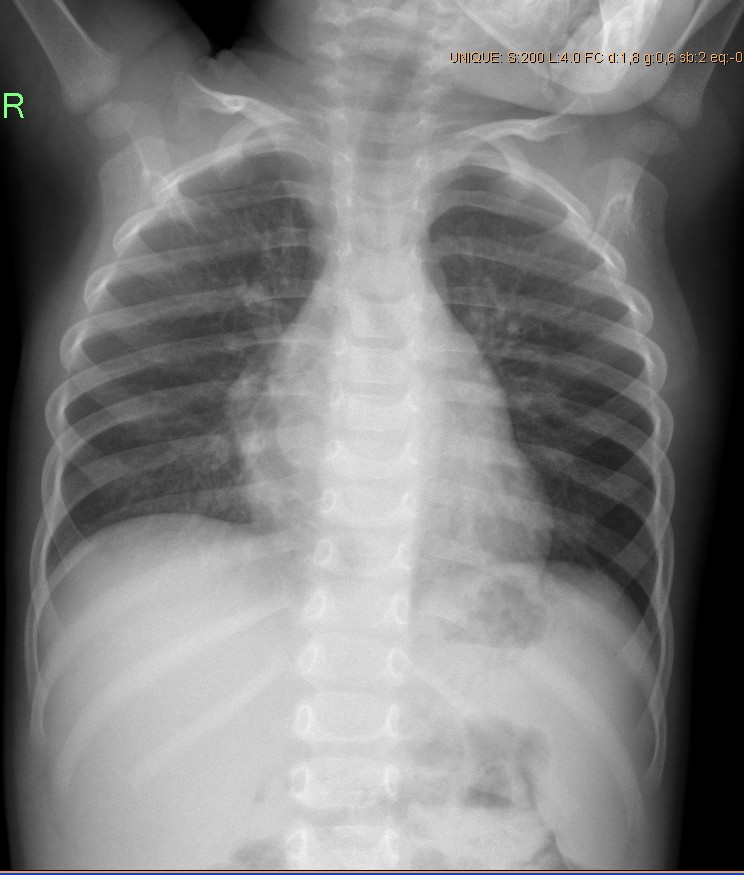

Нормальная рентгенограмма легких: что нужно знать

Раздел: Мудрость в объективе